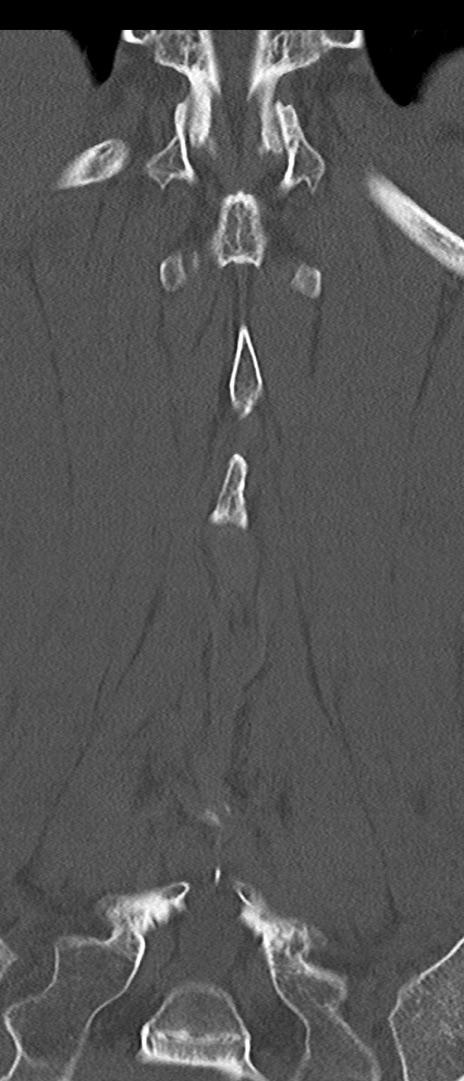

【整形】TIPS症例4 腰椎CT(冠状断像)

腰椎CT